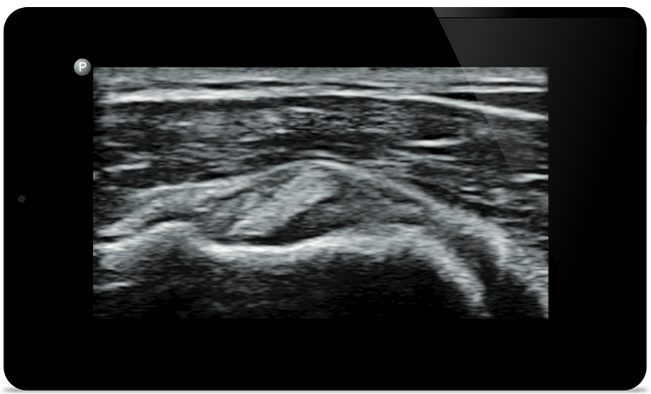

Lumify helpt u de fijne details in spieren, gewrichten, ligamenten, pezen en kraakbeen te zien om een nauwkeurigere diagnose te kunnen stellen.

Lumify kan u helpen patiënten van top tot teen te beoordelen, of het nu gaat om fasciitis plantaris, tendinitis of bursitis in de ligamentum patellae, of zelfs schouderinstabiliteit in de rotatorenmanchet.

SonoCT versterkt de beeldvorming van het echte weefsel, terwijl willekeurige artefacten worden geëlimineerd. Deze technologie produceert beelden die beter zijn dan conventionele beeldvorming bij tot wel 94% van de patiënten.